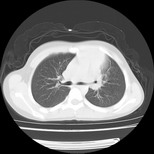

经过胸部穿刺活检为支原体感染。以下示抗支原体感染30天后所见,病灶明显缩小,临床症状消失: